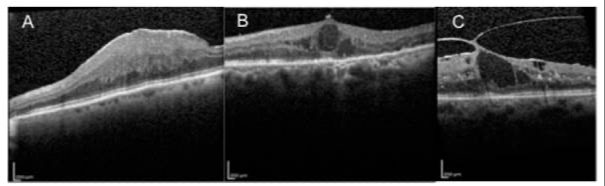

La morfología del edema orienta el manejo:

Quístico o difuso: respuesta a antiangiogénicos.

Seroso: evaluar componente isquémico y pronóstico visual.

Traccional: considerar vitrectomía.